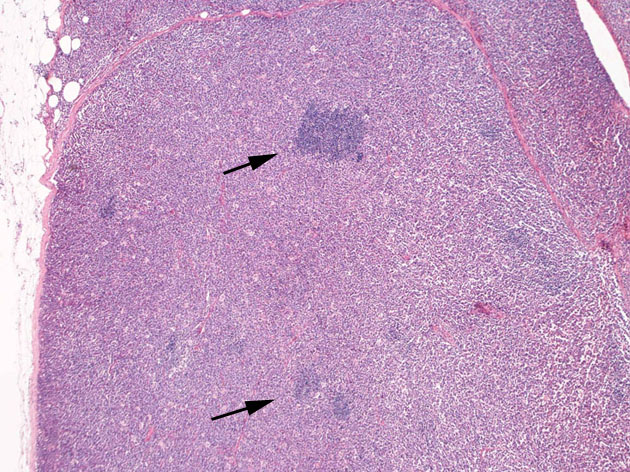

罹患リンパ節の基本構造は消失し腫瘍細胞のびまん性増殖で置換されている。非腫瘍性の小リンパ球(CD3+, CD4/8+)が濾胞様に散在して残る(Fig.01)。不整型または類円形の明るい核をもつmedium-sizeのリンパ球様細胞が密に増殖している。細胞質は乏しい(Fig.02)。CD68陽性macrophageが多く混在する部分が認められた(Fig.03)。

Fig.01Fig.02Fig.03